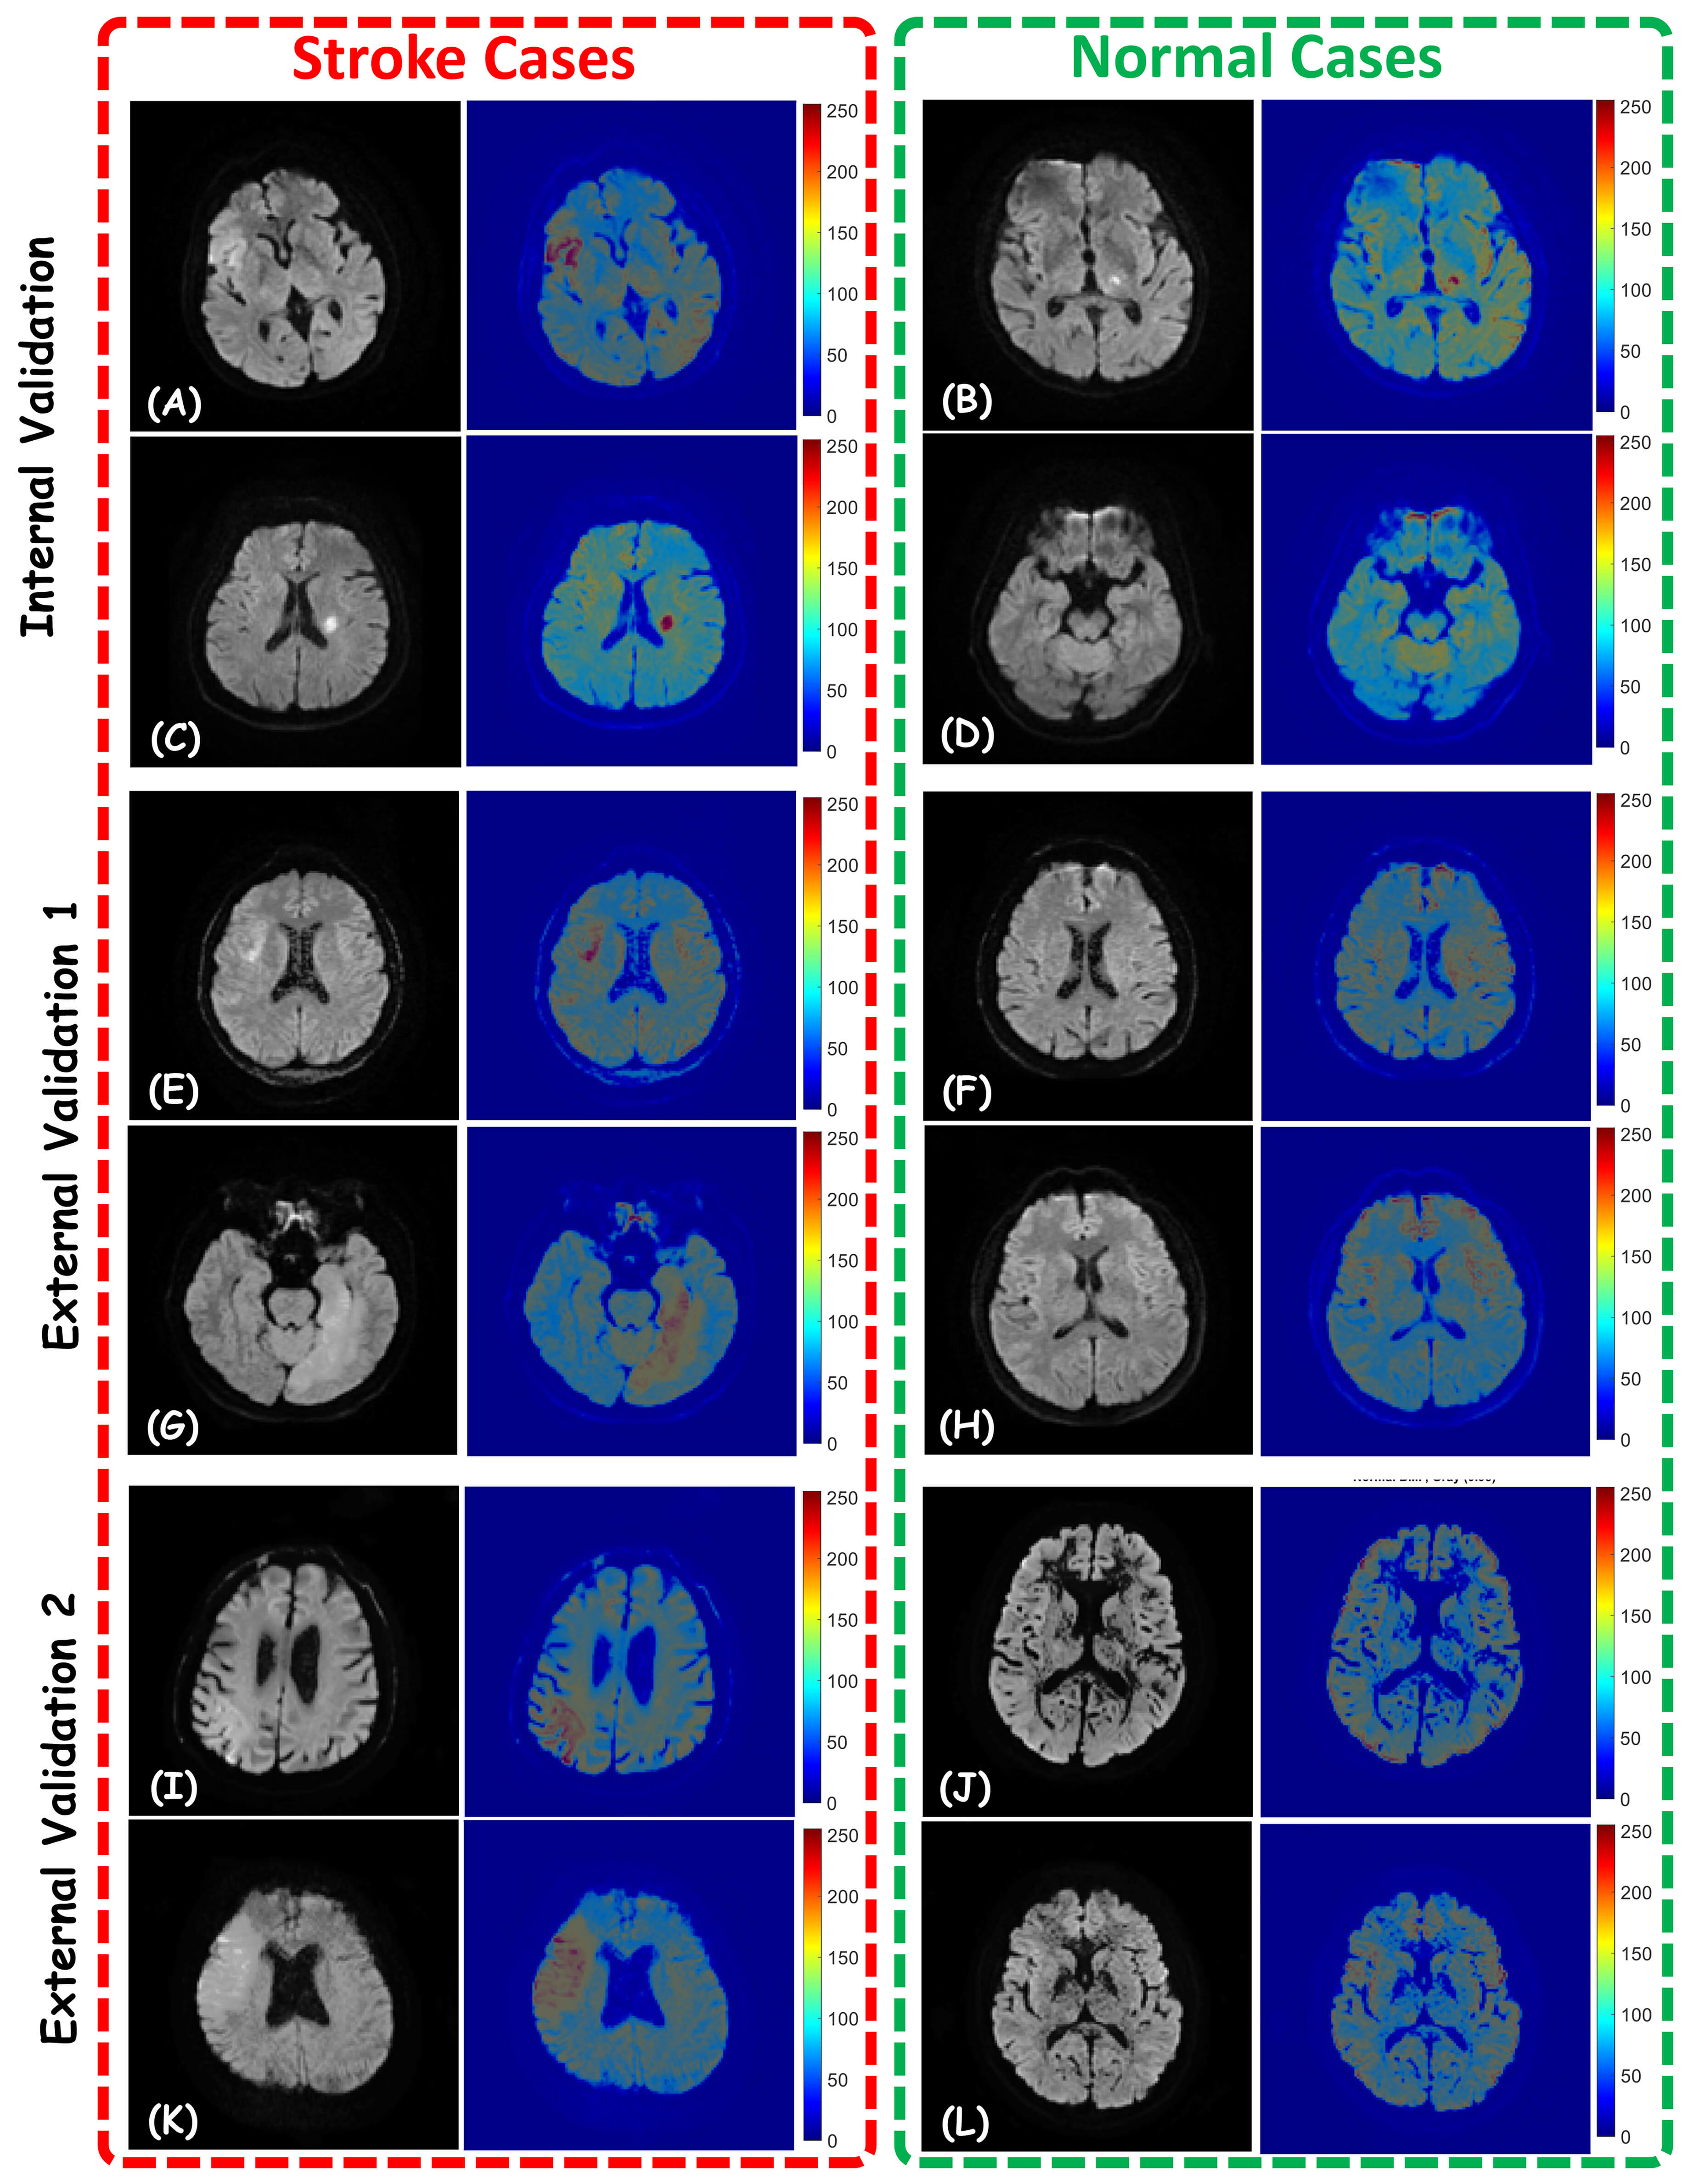

The proposed deep-learning model demonstrated excellent performance in diagnosing acute ischemic stroke patients with a sensitivity, specificity, and accuracy of 100% in the internal validation dataset. In addition, it could differentiate acute ischemic stroke patients from healthy controls with a sensitivity of 100%, specificity of 98% and accuracy of 99% in centers 2 and 3. ROC curves and AUC values with 95% CI and confusion matrices of the model are presented in Fig. 2 and Table 1, respectively. The Grad-CAMs of the proposed model for some cases in the three centers are shown in Fig. 3.

Fig. 3.

Visualization of Model Predictions using Gradient-weighted Class Activation Maps (Grad-CAMs). Representative diffusion-weighted imaging (DWI) slices and corresponding Grad-CAMs for stroke (left columns) and normal (right columns) cases across three distinct datasets: Internal Validation (A–D), External Validation 1 (E–H), and External Validation 2 (I–L). All cases were correctly diagnosed by the proposed AI model.

The Gradient-weighted Class Activation Mapping (Grad-CAM) method, as implemented in our study, demonstrated that the model focused on lesion areas when making decisions. Grad-CAM is a visualization technique that generates class-specific activation maps using the gradient information in the last convolutional layer to explain the decision-making processes of deep convolutional neural networks (CNNs). In CNN models trained for ischemic stroke detection in brain MRI images, the Grad-CAM method enables insightful analysis by localizing the spatial regions that guide the model’s prediction and offers the opportunity to assess the clinical relevance of the decision mechanism. Specifically, when contrasting ischemic lesions and normal tissues in diffusion-weighted images, heat maps derived from Grad-CAM can directly illustrate the location and extent of the lesion. In a study by Lai et al. [20], Grad-CAM outputs, which allow for visual assessment of the location and extent of lesions in diffusion-weighted images, are used as an important tool to evaluate whether the model correctly processes pathological regions. Other recent studies in the literature have also shown that Grad-CAM improves both model performance and explainability in automatic ischemic stroke detection systems [21, 22]. Consequently, Grad-CAM not only fosters classification accuracy but also assumes a pivotal role in the implementation of AI-based clinical decision support systems. In a small number of cases, Grad-CAM visualizations highlighted regions adjacent to, rather than directly overlapping with, radiologists’ annotated lesions. Such discrepancies may reflect sensitivity to subtle diffusion changes, partial volume effects, or image noise, and underscore the complementary role of AI-based attention maps rather than direct lesion delineation.